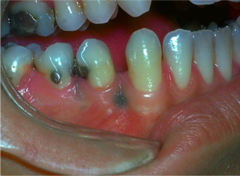

A grey, blue-black flat lesion on buccal mucosa- also known ask focal argyrosis

Front

Amalgam tattoo

Back